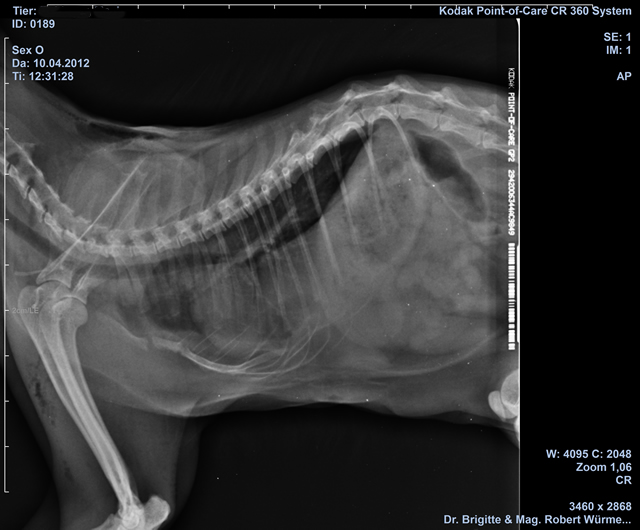

Röntgendiagnostik / Ultraschall

Unsere moderne Röntgenanlage ermöglicht die Aufnahme von Röntgenbildern auf höchstem Niveau.

- HD/ED Röntgen: zugelassen für SVÖ und Hirtenhunde, ÖKV